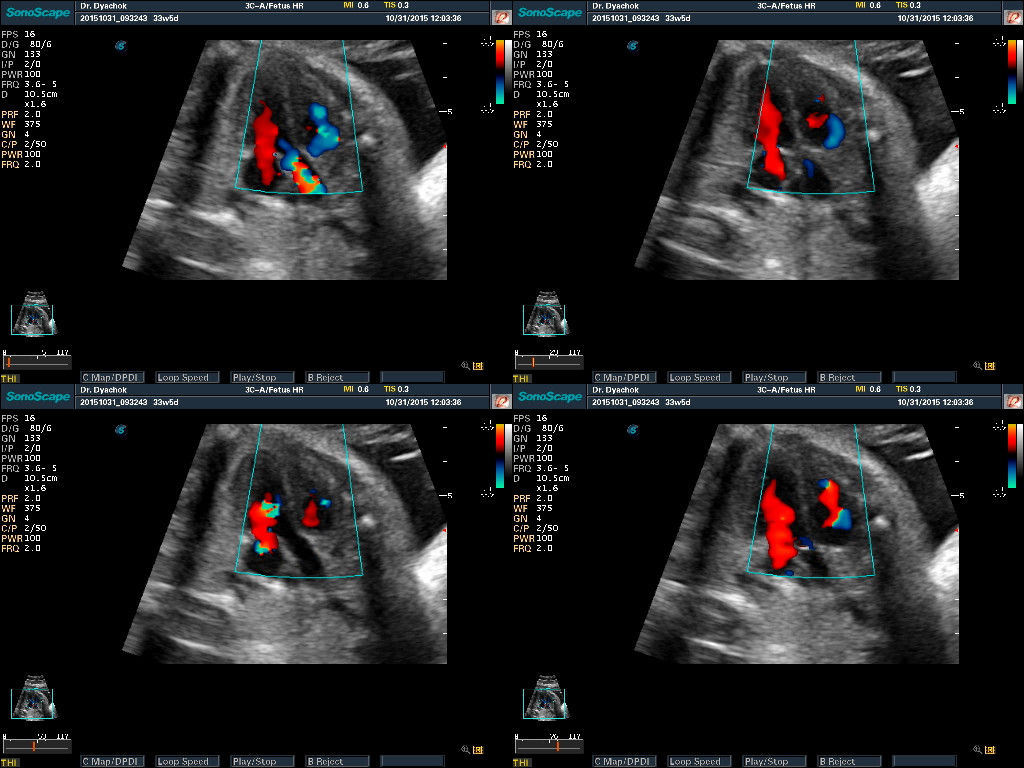

- 4D – режим трехмерной реконструкции в реальном времени

- Расчеты для акушерства, гинекологии, ангиологии, урологии, ортопедии, поверхностных, абдоминальных органов, кардиологии, головного мозга и сердца плода (в том числе STIC), вывода кривых роста плода, автоматический анализ толщины комплекса интима-медиа